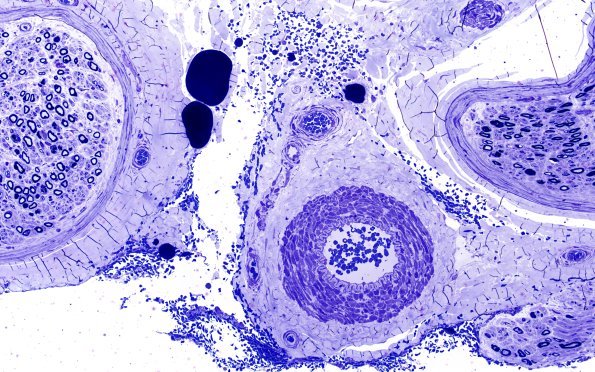

9A2,3 This vessel is more compellingly an arteriole with a prominent internal elastic lamina. (plastic section)